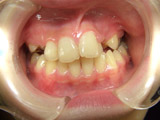

1番左の写真は初診時でH19 4月です。

左上の2番目の歯が内側に入ってしまい歯並びが悪くなっています。